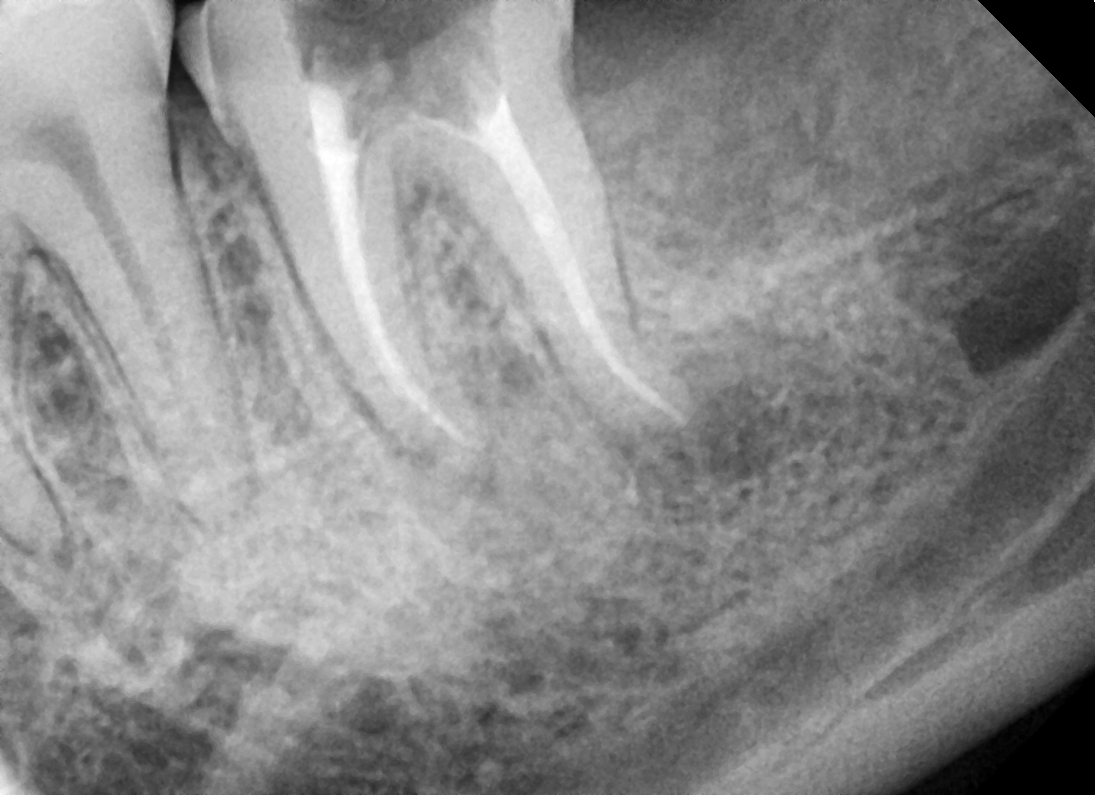

• Obturation: Filling the root canal

• Once the bacteria and infection are under control (no more signs and symptoms of soreness or discomfort from the tooth), the root filling can be done.

• Irrigate the tooth with antibacterial solutions, dry the tooth, Gutta Percha (rubber points) should be placed into the root canals.

• Once the Gutta Percha is placed, a temporary filling on the tooth or a permanent filling on the tooth can be placed.

Gallery